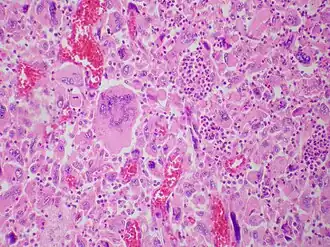

Description de l'image Giant cell carcinoma - Case 284 (13107156794).jpg.

Le carcinome pulmonaire à cellules géantes est un sous-type de carcinome pulmonaire à grandes cellules (ou carcinome anaplasique à grandes cellules).